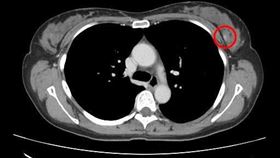

熟女摸乳房多顆腫塊 良性纖維瘤竟變乳癌

每年10月為國際乳癌防治月,光田綜合院區大甲院區分享...